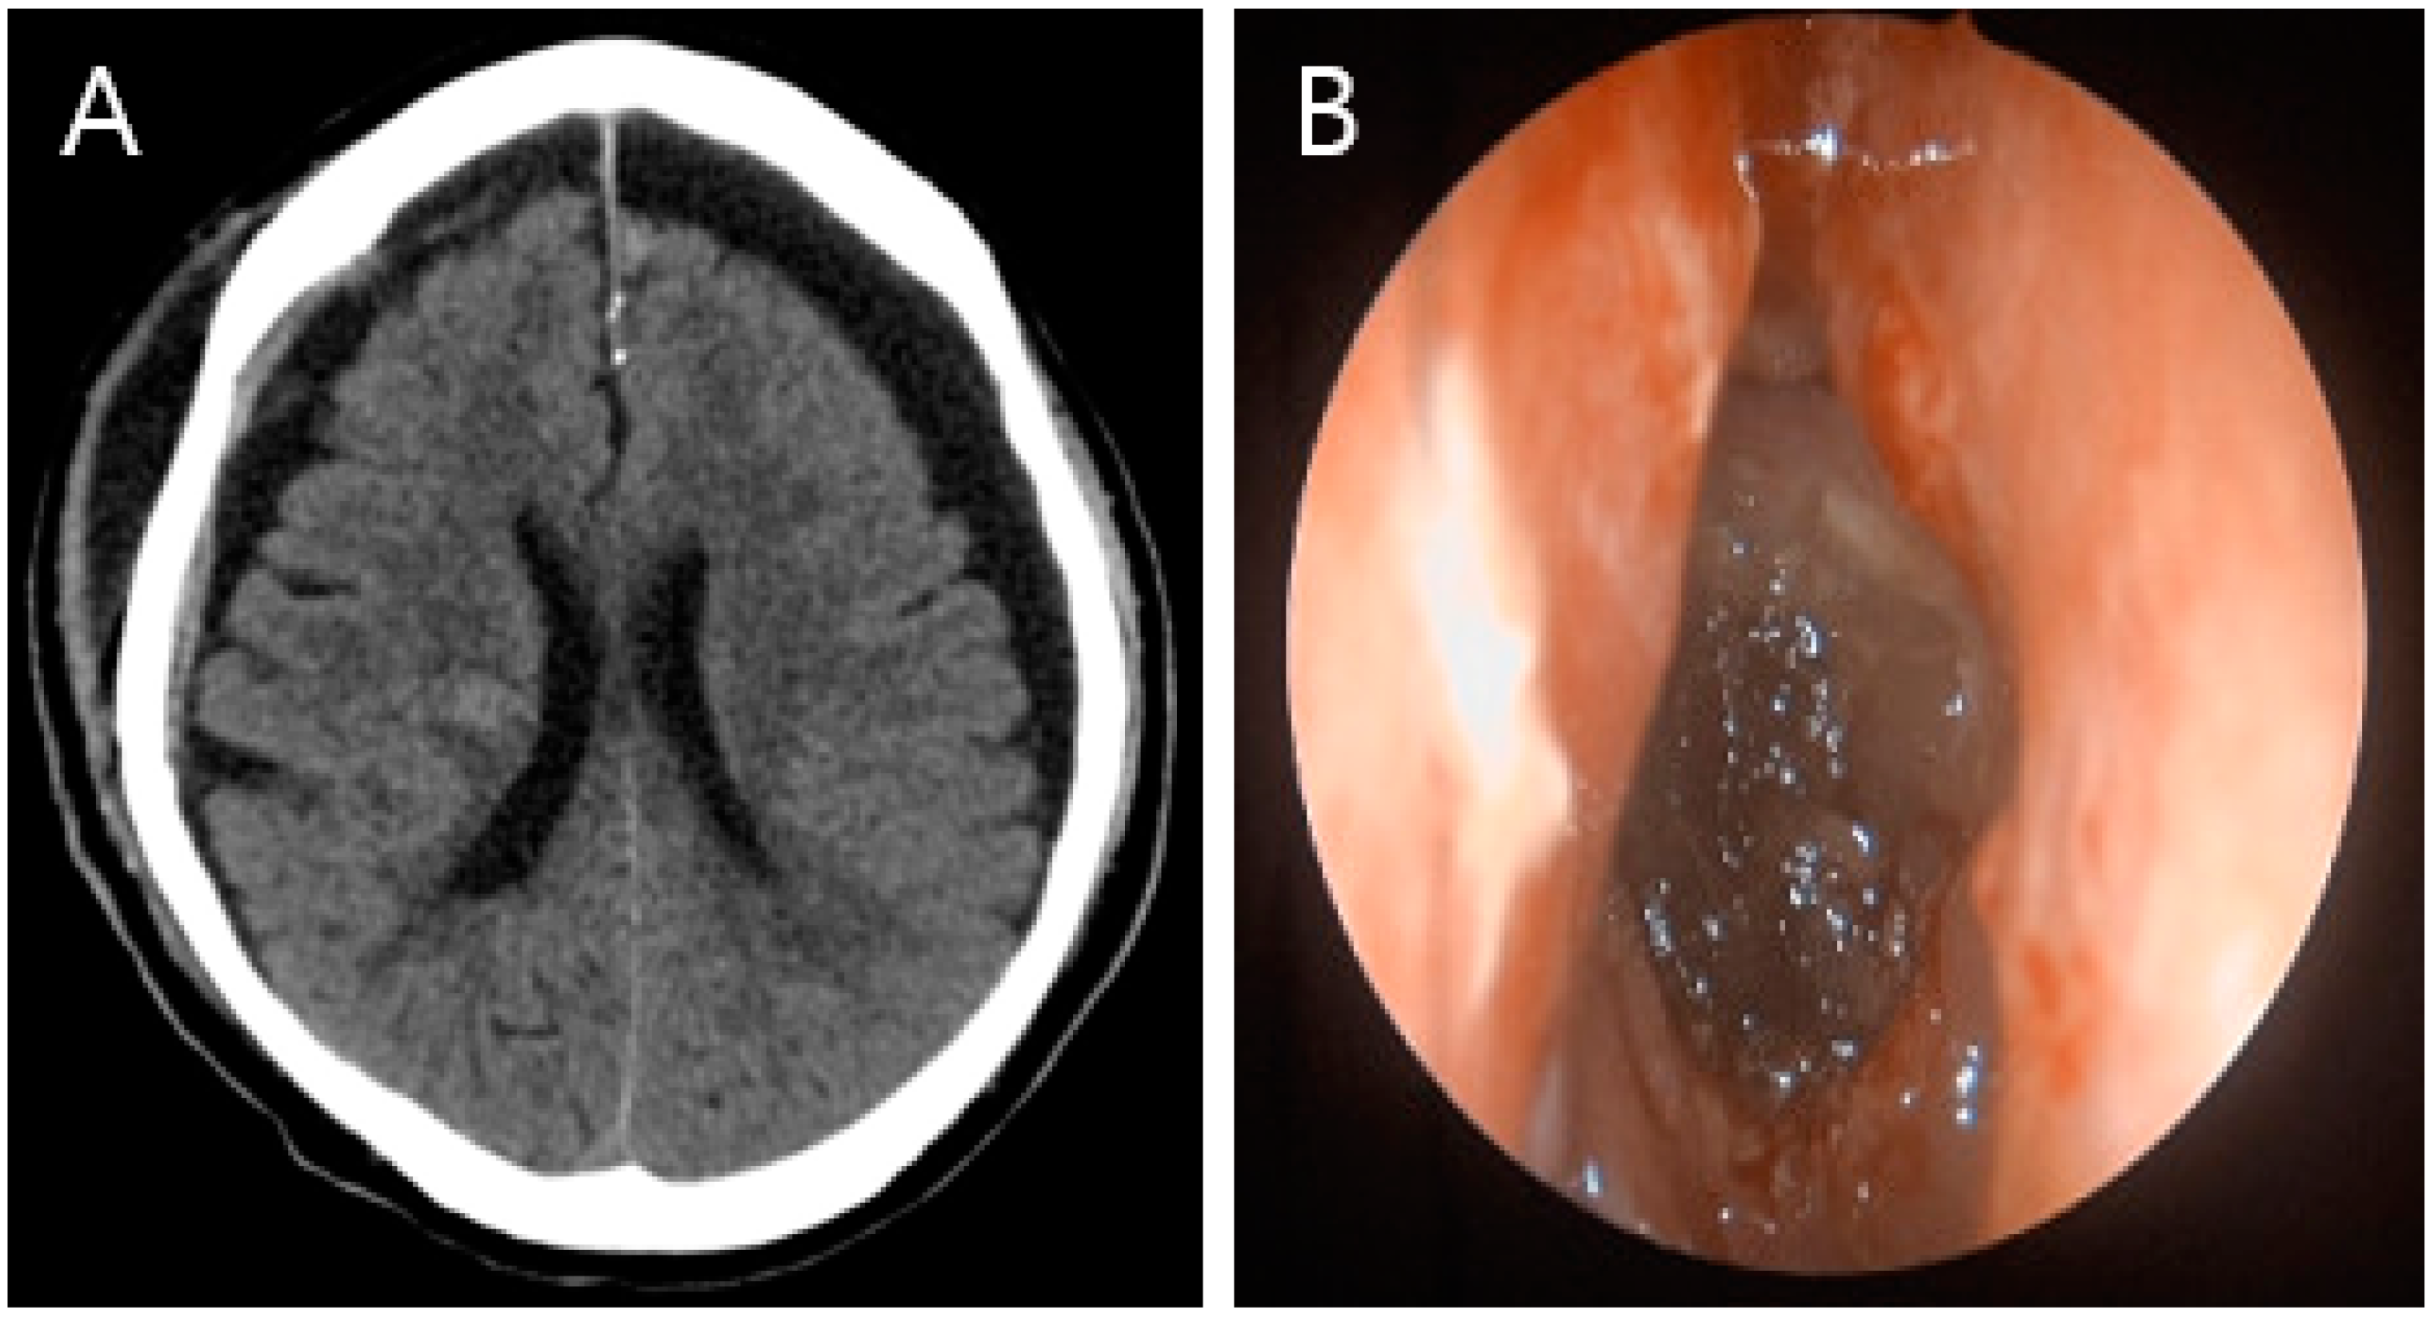

One-month follow-up. (A) Brain CT image, showing no specific findings except for bilateral hygroma. (B) Nasal endoscopy, showing that the defective area healed well without any specific findings.